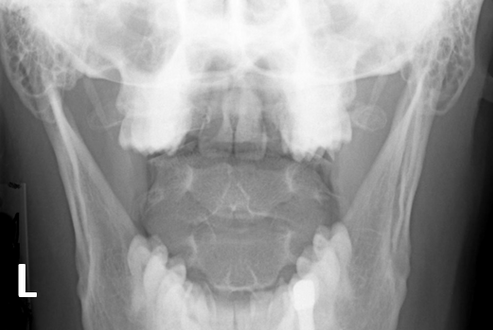

C-Spine Odontoid: Which options are true?

A repeat with more flexion of the head/neck is needed

A repeat with more extension of the head/neck is needed

The R/L marker is incorrect

This is a well-positioned radiograph; no repeat required.

2 and 3

Repeat with more extension of the head/neck is needed

R/L marker is incorrect

Which of the following statements are correct regarding the Odontoid radiograph below?

The atlantoaxial articulation is well demonstrated

The odontoid process is incompletely visualized

More flexion is required to move upper incisors inferiorly

More extension is required to move base of skull more inferiorly

1, 2, and 3